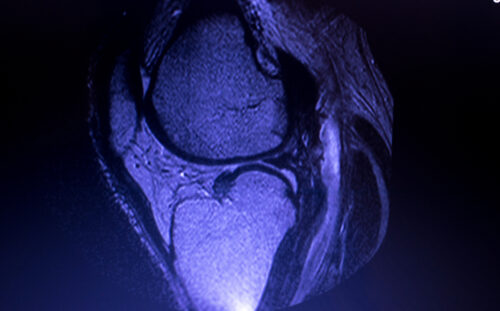

- Temel artroplasti eğitimi

- TOTEK XVIII. Diz Ekleminde temel artroskopi eğitimi